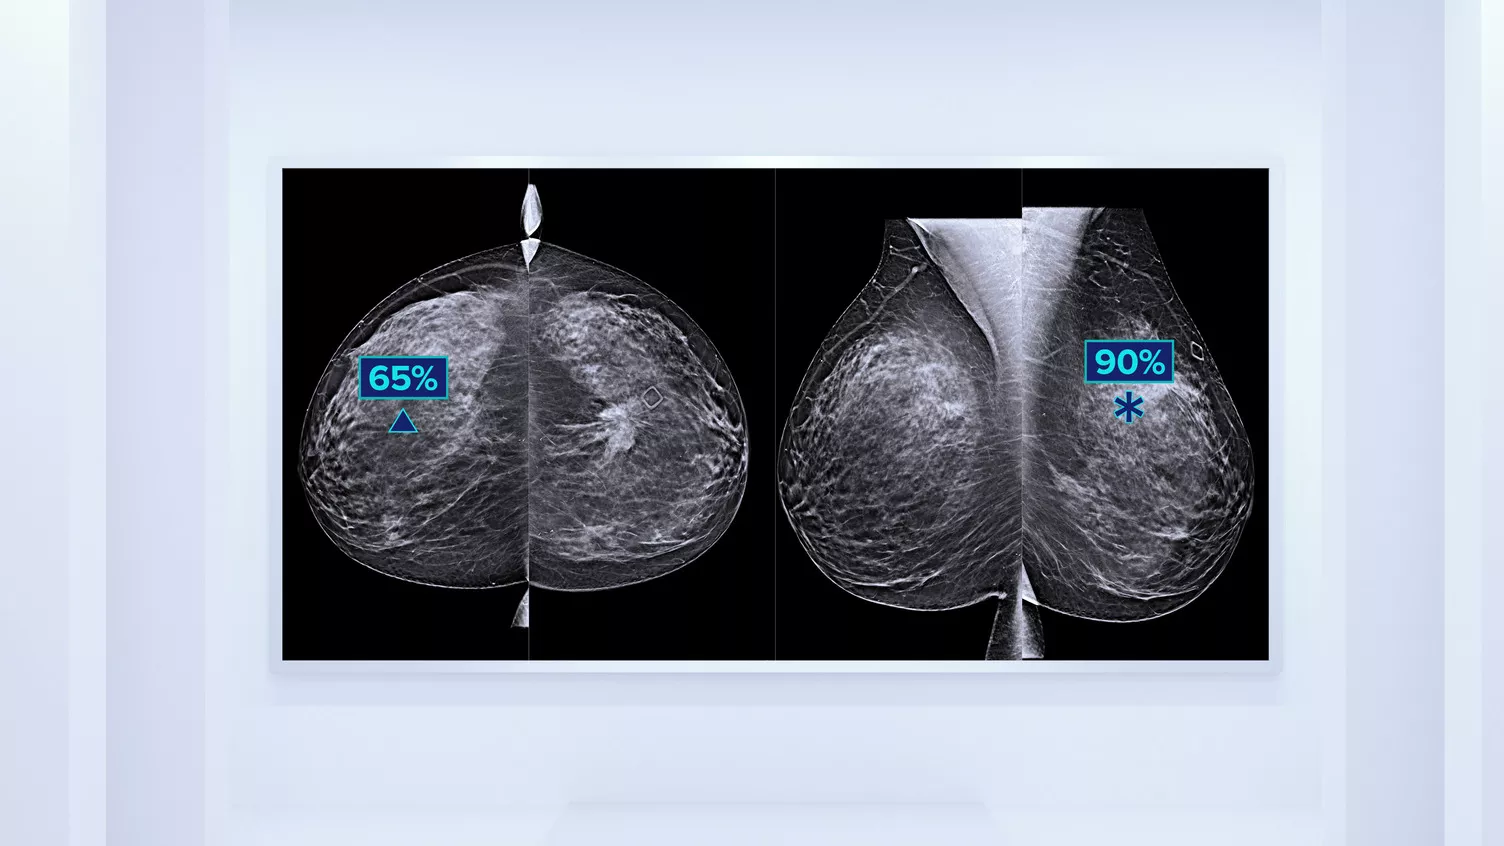

Higher breast density is known to increase a woman’s risk for breast cancer.1 The need for accurate, unbiased analysis is therefore critical. Powered by machine learning, Quantra technology software analyses both 2D™ and tomosynthesis images for distribution and texture of parenchymal tissue. It categorises breasts in four breast composition categories consistent with guidance from the American College of Radiology (ACR) BI-RADS Atlas 5th Edition.2

In addition to volume, pattern and texture of fibroglandular tissue may play just as an important role in mammographic cancer risk prediction.3-5 By analysing and categorising breast texture and pattern, our technology can deliver the accurate information you need to achieve more consistent and reliable scoring and confidently design patient-specific screening.

Objective machine learning algorithm that assigns breast density category based on analysis of breast tissue texture and patterns.

Quantra software’s unbiased algorithm analyse both 2D and tomosynthesis images to support your analysis by:

- Overcoming subjectivity in visual assessment, providing more consistent, and more reliable scoring.*